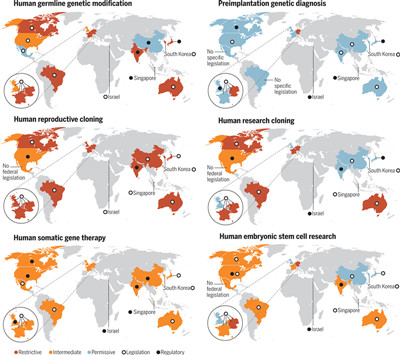

Cell子刊:精准医学的光明未来

2015年1月20日,美国总统奥巴马在国情咨文中提出“精准医学计划”,希望精准医学可以引领一个医学新时代。精确医学是利用来自基因组序列到健康档案的大量临床数据,来确定药物如何以不同的方式影响人们。